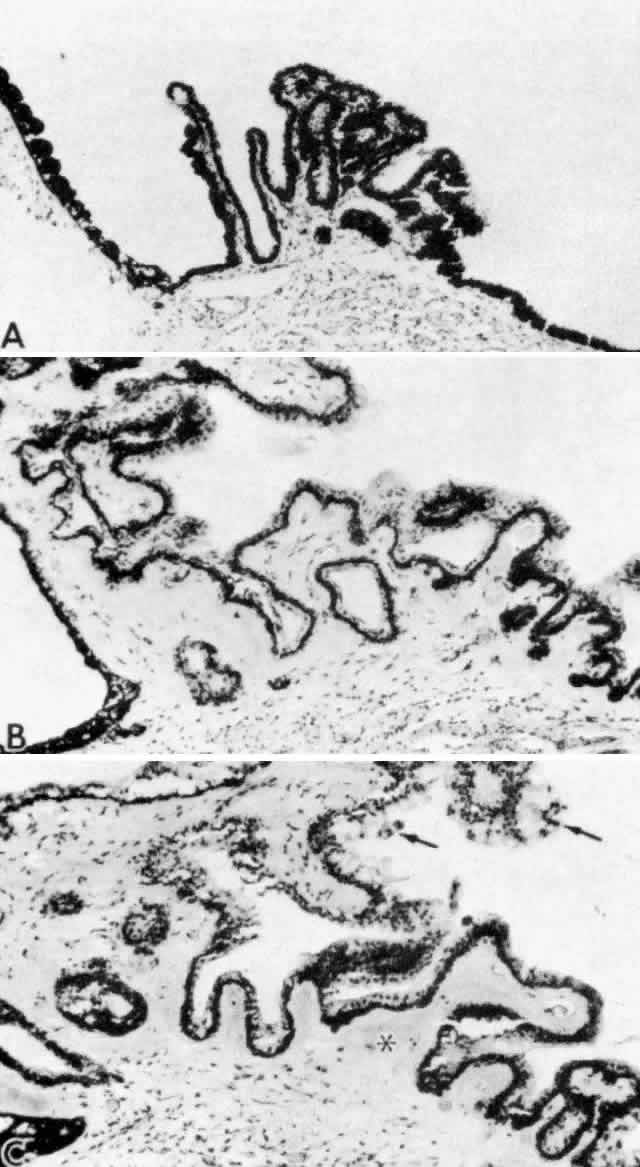

Fig. 13. Ciliary nonpigmented epithelium. A. Anterior pars plicata, age 3. (hematoxylin-eosin, X 800) B. Posterior pars plicata with areas of thickened, pigmented

epithelium, age 3. m, ciliary muscle (hematoxylin-eosin, X 800) C. Nodular

proliferation of the nonpigmented epithelium appears

as small cellular caps over the surface at age 70. Z, zonule. (hematoxylin-eosin, X 400) D. Distorted epithelium of pars plana shows evidence

of traction in both anterior and posterior directions (adult). (hematoxylin-eosin, X 400) Fig. 13. Ciliary nonpigmented epithelium. A. Anterior pars plicata, age 3. (hematoxylin-eosin, X 800) B. Posterior pars plicata with areas of thickened, pigmented

epithelium, age 3. m, ciliary muscle (hematoxylin-eosin, X 800) C. Nodular

proliferation of the nonpigmented epithelium appears

as small cellular caps over the surface at age 70. Z, zonule. (hematoxylin-eosin, X 400) D. Distorted epithelium of pars plana shows evidence

of traction in both anterior and posterior directions (adult). (hematoxylin-eosin, X 400)

|

in number, and the cells become slightly smaller (Fig. 12). In the pars plicata the NPE cells are cuboidal, 12 to 15 μm in width, with

central nuclei (Figs. 13A and 13B). The knobbiness that develops during aging is due to small nodular proliferations

of NPE cells, especially on the minor plicae (Fig. 13C). In the young eye the cells of the pars plana are also cuboidal, but

with growth they become thinner and more columnar, sometimes reaching

up to 30 μm in height and 5 to 10 μm in width (Fig. 13D). In the posterior half of the pars plana, some NPE cells tilt forward

as though responding to anterior zonular traction, while others may be

inclined posteriorly, suggesting complex vectors of force in this region. The

nuclei are vertically oval and lie near the apex of the cells. The

epithelium here becomes very irregular with aging, showing hyperplastic

toothlike cell processes intertwining and extending up into the

vitreous and among the zonular fibers. At the ora serrata the ciliary

NPE joins the retina abruptly, highlighting the difference in thickness

of these two layers (Fig. 14).  Fig. 12. Frontal view of a ciliary process at its junction with iris, showing conversion